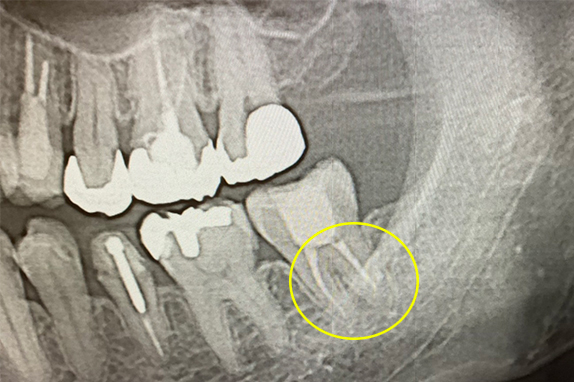

CASE 01 マイクロエンド(精密根管治療)+インプラント治療

-

- 主訴

- 痛くて噛めない(50代女性)

-

- 回数期間

- 6回 約3ヶ月

-

- 治療法

- マイクロエンド(精密根管治療)+インプラント

-

- 治療費用

- 約65万円(税抜)

右の奥歯が痛くて噛めないという主訴で来院。7番をマイクロエンドで完全し6番にインプラントを埋入したケースです。

<リスク・副作用>

術後は顔面の腫脹に加え、青あざができる場合があります。過度な衝撃や咬合を加えると補綴物の破折、脱落の可能性があります。